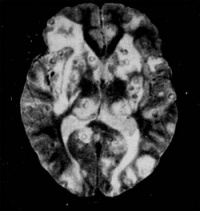

MRI:

可以显示不同时期的囊虫病灶,脑实质内脑囊虫可表现为结节形、环形或囊形,有时可显示头节,增强扫描可强化,有不同程度的脑水肿。脑室内活囊虫特别是在矢状面和冠状面上,T1加权像上囊虫呈低信号,比脑脊液信号略高,其囊壁呈高信号,头节也呈高信号。MRI对钙化的显示不如CT。